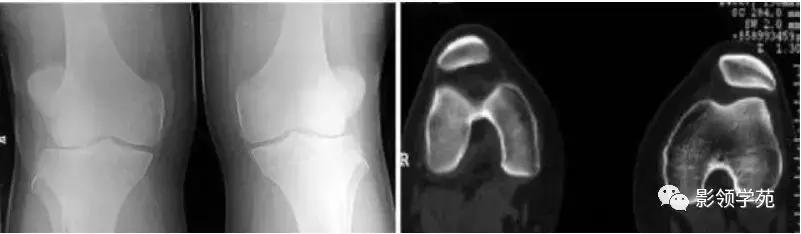

5、分裂 (二分)髌骨

常见于儿童,多双侧性。 一般认为是正常骨化的变异,可在十几岁时融合。

症状:运动时疼痛或运动后疼痛,膝关节屈曲时疼痛、下跪时疼痛,上下楼梯时疼痛,行走时疼痛,受冷时疼痛。

分裂部扣击痛:可诱发有症状的分裂髌骨的疼痛,无症状者阴性。分裂骨片局部骨性隆起。 股四头肌萎缩, 髌骨摩擦音,大多无关节积液、跛行和关节活动度受限。有时需与骨折鉴别。